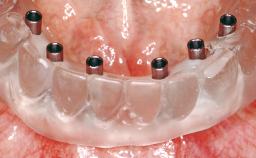

Immediate Loading of Six Implants in the Maxilla and Final Restoration with a Full-Arch CAD/CAM Zirconia FDP

A 63-year-old male patient was referred for a consultation and treatment of partial edentulism in the maxilla. The patient presented with residual anterior teeth and declined a partial removable prosthesis. He reported that the maxillary posterior teeth had been extracted due to mobility and periodontal disease two months before the consultation. The patient’s chief complaint was that his residual maxillary teeth were mobile and that he was unable to chew. The patient’s desire was a stable and comfortable fixed maxillary rehabilitation. The patient was a light smoker (fewer than 10 cigarettes/ day), and his medical history was without significant findings. He was not on any regular medication at the time of consultation. The extraoral examination revealed a normal physiognomy with a correct distribution of the facial thirds. The patient presented a low lip line, and the transition line between teeth and soft tissues was not exposed during a forced smile.

# of Implants 6

Type of Implants One-Piece

Modality 6+ implants with immediate loading